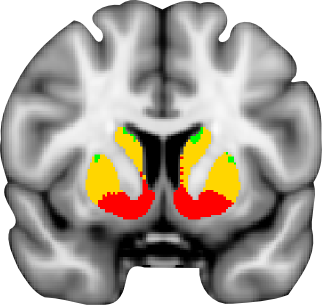

Oxford-GSK-Imanova structural and connectivity striatal atlases

Connectivity atlas

A probabilistic atlas of sub-striatal regions, segmented according to their white-matter connectivity to cortical areas. This connectivity atlas reports anatomical connection from points in the striatum to each of 7 cortical zones obtained using probabilistic diffusion tractography in multiple subjects. For more details see the Striatal Connectivity Atlas web page.

Structural atlas

Atlas of sub-striatal regions, segmented according to the anatomical structure. Striatum is divided into caudate, putamen and ventral striatum according to the guidelines described by Tziortzi et al (2011). The sub-regions were manually delineated on the non-linear MNI152 template. For more details see the Structural Striatal Atlas web page.